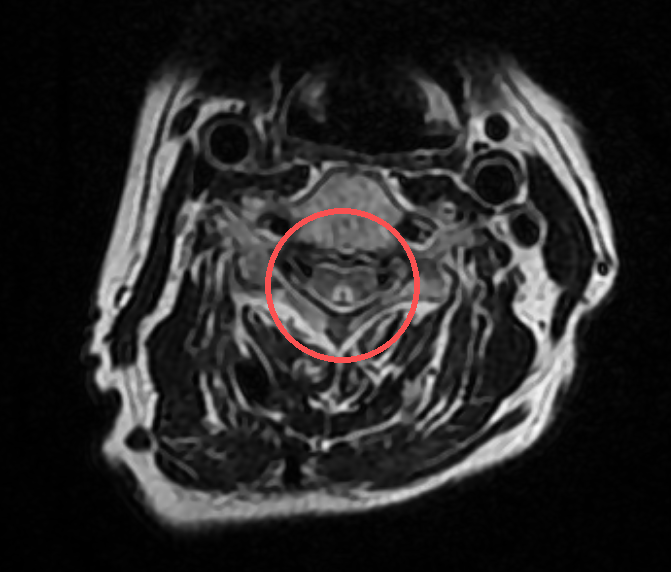

李阿姨的检查结果很典型,颈椎磁共振可见在颈段脊髓后方可见对称的、呈倒「V」字形的异常高信号,脊髓外形通常不肿胀。

要诊断是否患有「脊髓亚急性联合变性」,医生会通过简单的体格检查,比如用音叉测试脚踝的震动感、抽血检测维生素 B12 水平,再结合颈椎磁共振,看脊髓神经是否受损来明确判断。